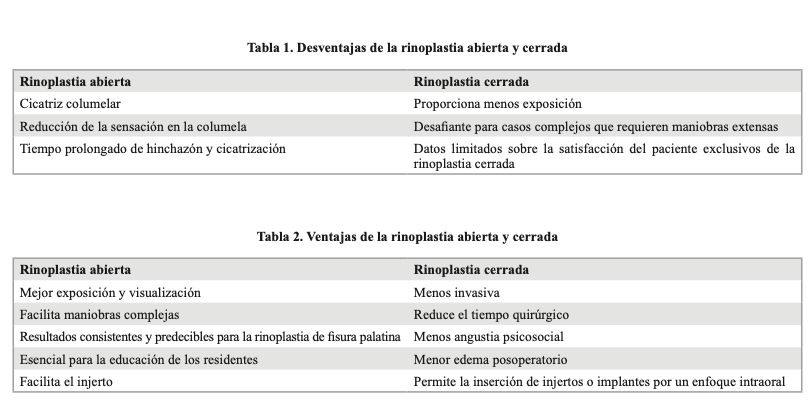

Sebastián Castro, Luis Cabezas, Felipe Cardemil

|

|

|